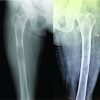

An 80-year-old female presented with a history of gradually increasing swelling in the left leg for the past 2 months and insidious onset pain of 1 week duration. There was no significant history of trauma. On examination, there was minimal tenderness over the middle third of the anterior aspect of the leg. Blood investigations showed an increased serum calcium level of 14 mg/dL (normal 8.4–10.7 mg/dL), a serum albumin level of 4.3 g/dL (normal 3.4–4.8 g/dL), a serum PTH level of 1380 pg/mL (normal 7–53 pg/mL), and a vitamin D3 level of 28 pg/mL (normal 25–45 pg/mL). Radiological examination showed multiple lytic areas of destruction in the entire length of the left tibia, distal femur, and tarsal bones. A nuclear scan revealed enhanced activity in the right parathyroid gland, and a diagnosis of PHPT was made. She underwent a biopsy of the bony lesion, which was followed by a hemithyroidectomy. A prophylactic nailing of the left tibia was done since the scoring as per Mirel’s criteria was 10 (Table 3).

Histopathological findings were consistent with Brown’s tumor. Serial calcium monitoring was done to monitor for hypocalcemic episodes and was treated with intravenous calcium therapy. The post-operative care included static quadriceps exercises and was initiated along with walking frame-assisted non-weight-bearing mobilization. After 6 weeks, blood parameters were repeated and were found to be normal. The patient was kept non-weight-bearing for 12 weeks, followed by gradual partial-weight-bearing with walker assistance. She was asymptomatic at 6 months of follow-up with near-normal serum parameters and was permitted to walk with a stick support. At 1 year, the fracture healed completely, and she was painless. The case details of the demographics, clinical presentation, laboratory and radiological signs, and treatment given to each of the 4 patients are summarized in Table 1.